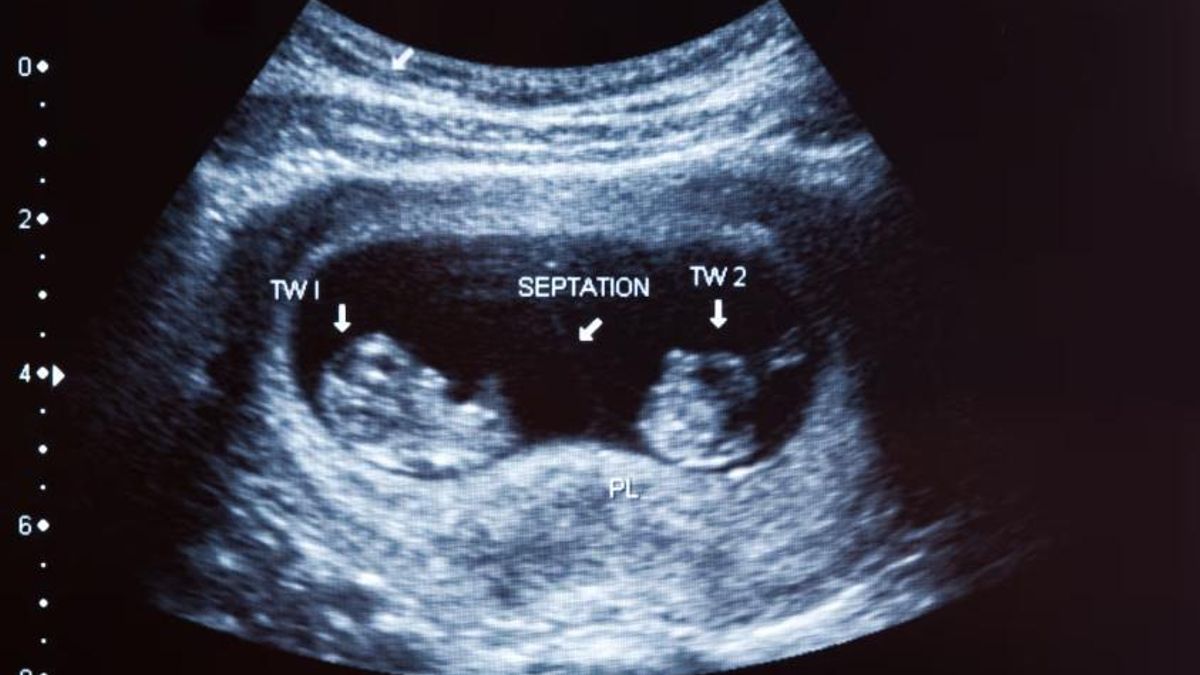

Los especialistas estiman que los embarazos gemelares representan alrededor del 2% de los nacimientos a nivel mundial.

Los especialistas estiman que los embarazos gemelares representan alrededor del 2% de los nacimientos a nivel mundial, una coincidencia numérica que suele destacarse al hablar de esta efeméride. Si bien los gemelos nacen con pocos segundos de diferencia y comparten el mismo útero, con el paso de los años comienzan a diferenciarse en rasgos físicos y de personalidad.

Desde el punto de vista médico, los embarazos múltiples presentan distintas variantes. Además de los gemelos idénticos, existen los dicigóticos, conocidos como mellizos, que se producen cuando dos óvulos distintos son fecundados por dos espermatozoides diferentes. En estos casos, el parecido es similar al de cualquier par de hermanos.